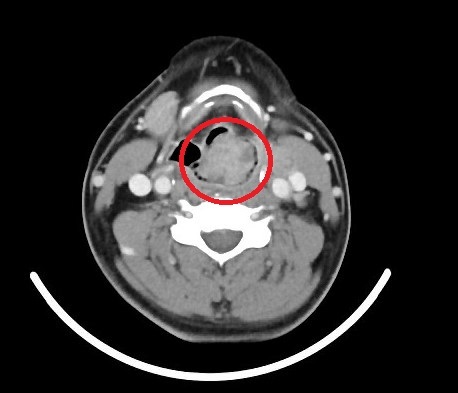

▲ 男子長期沙啞就醫檢查竟已罹患下咽癌第四期(圖/澄清醫院提供)

王姓男子在澄清醫院求診時,耳鼻喉科醫師林奐宇發現他講話聲音沙啞,且呼吸急促。經內視鏡檢查後,發現喉嚨有一顆近3公分大的腫瘤,幾乎封住呼吸道,情況危急。進一步診斷後,確認為下咽癌第四期。